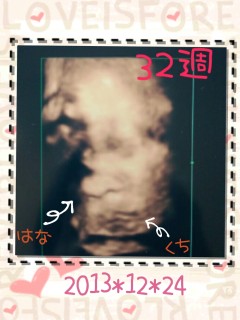

写真:32w2d:anmamaさん:1994g

1994gの女の子です☆ 口半開き、目も半開き、 完全に私の癖を引き継いだようww しかし我が子は可愛いですな^^